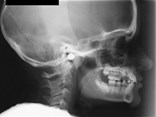

X-Rays and Cephalometric Tracings

pan xray ceph tracing measurements patienthist

Panoramic Intraoral Lateral Ceph Ceph Tracing Cephalometric Summary Patient History